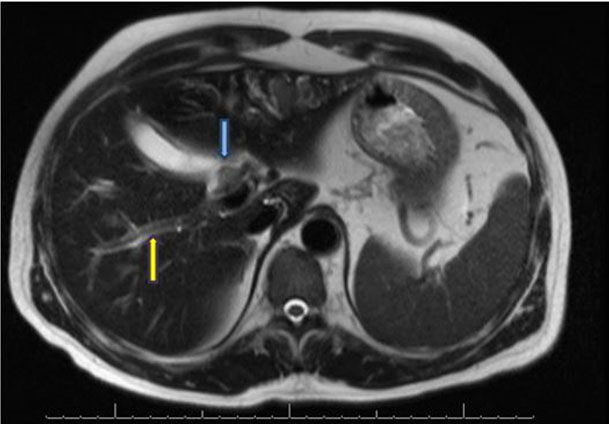

Repeat CECT scan of chest and abdomen was done which showed left sided minimal pleural effusion and underlying collapse of lung. There was evidence of intra- and peri-pancreatic necrotic collections. As compared with previous CT scan, there was organization of collections (Figure 2). Intravenous antibiotics were upgraded and inflammatory markers and blood cultures were sent. On day 19 of illness, she had recurrence of fever. Blood cultures and urine culture were sterile after 48 hours. Repeat real time qualitative PCR was negative for COVID-19 on day 19 of hospital admission. In view of fever and organized collection she underwent ultrasonography guided percutaneous drainage of collection and her fever subsided. She is still under follow-up with drain in situ.

Figure 2: Acute necrotizing pancreatic collection (three week of pancreatitis).